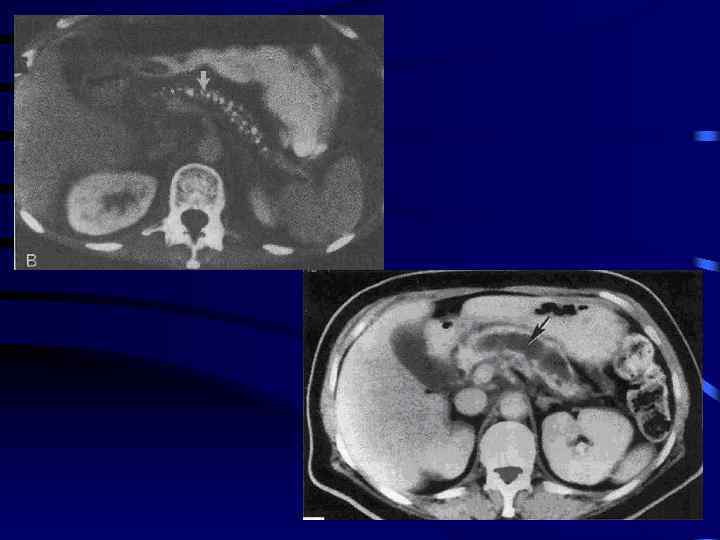

Разрыв поджелудочной железы по перешейку (КТ)